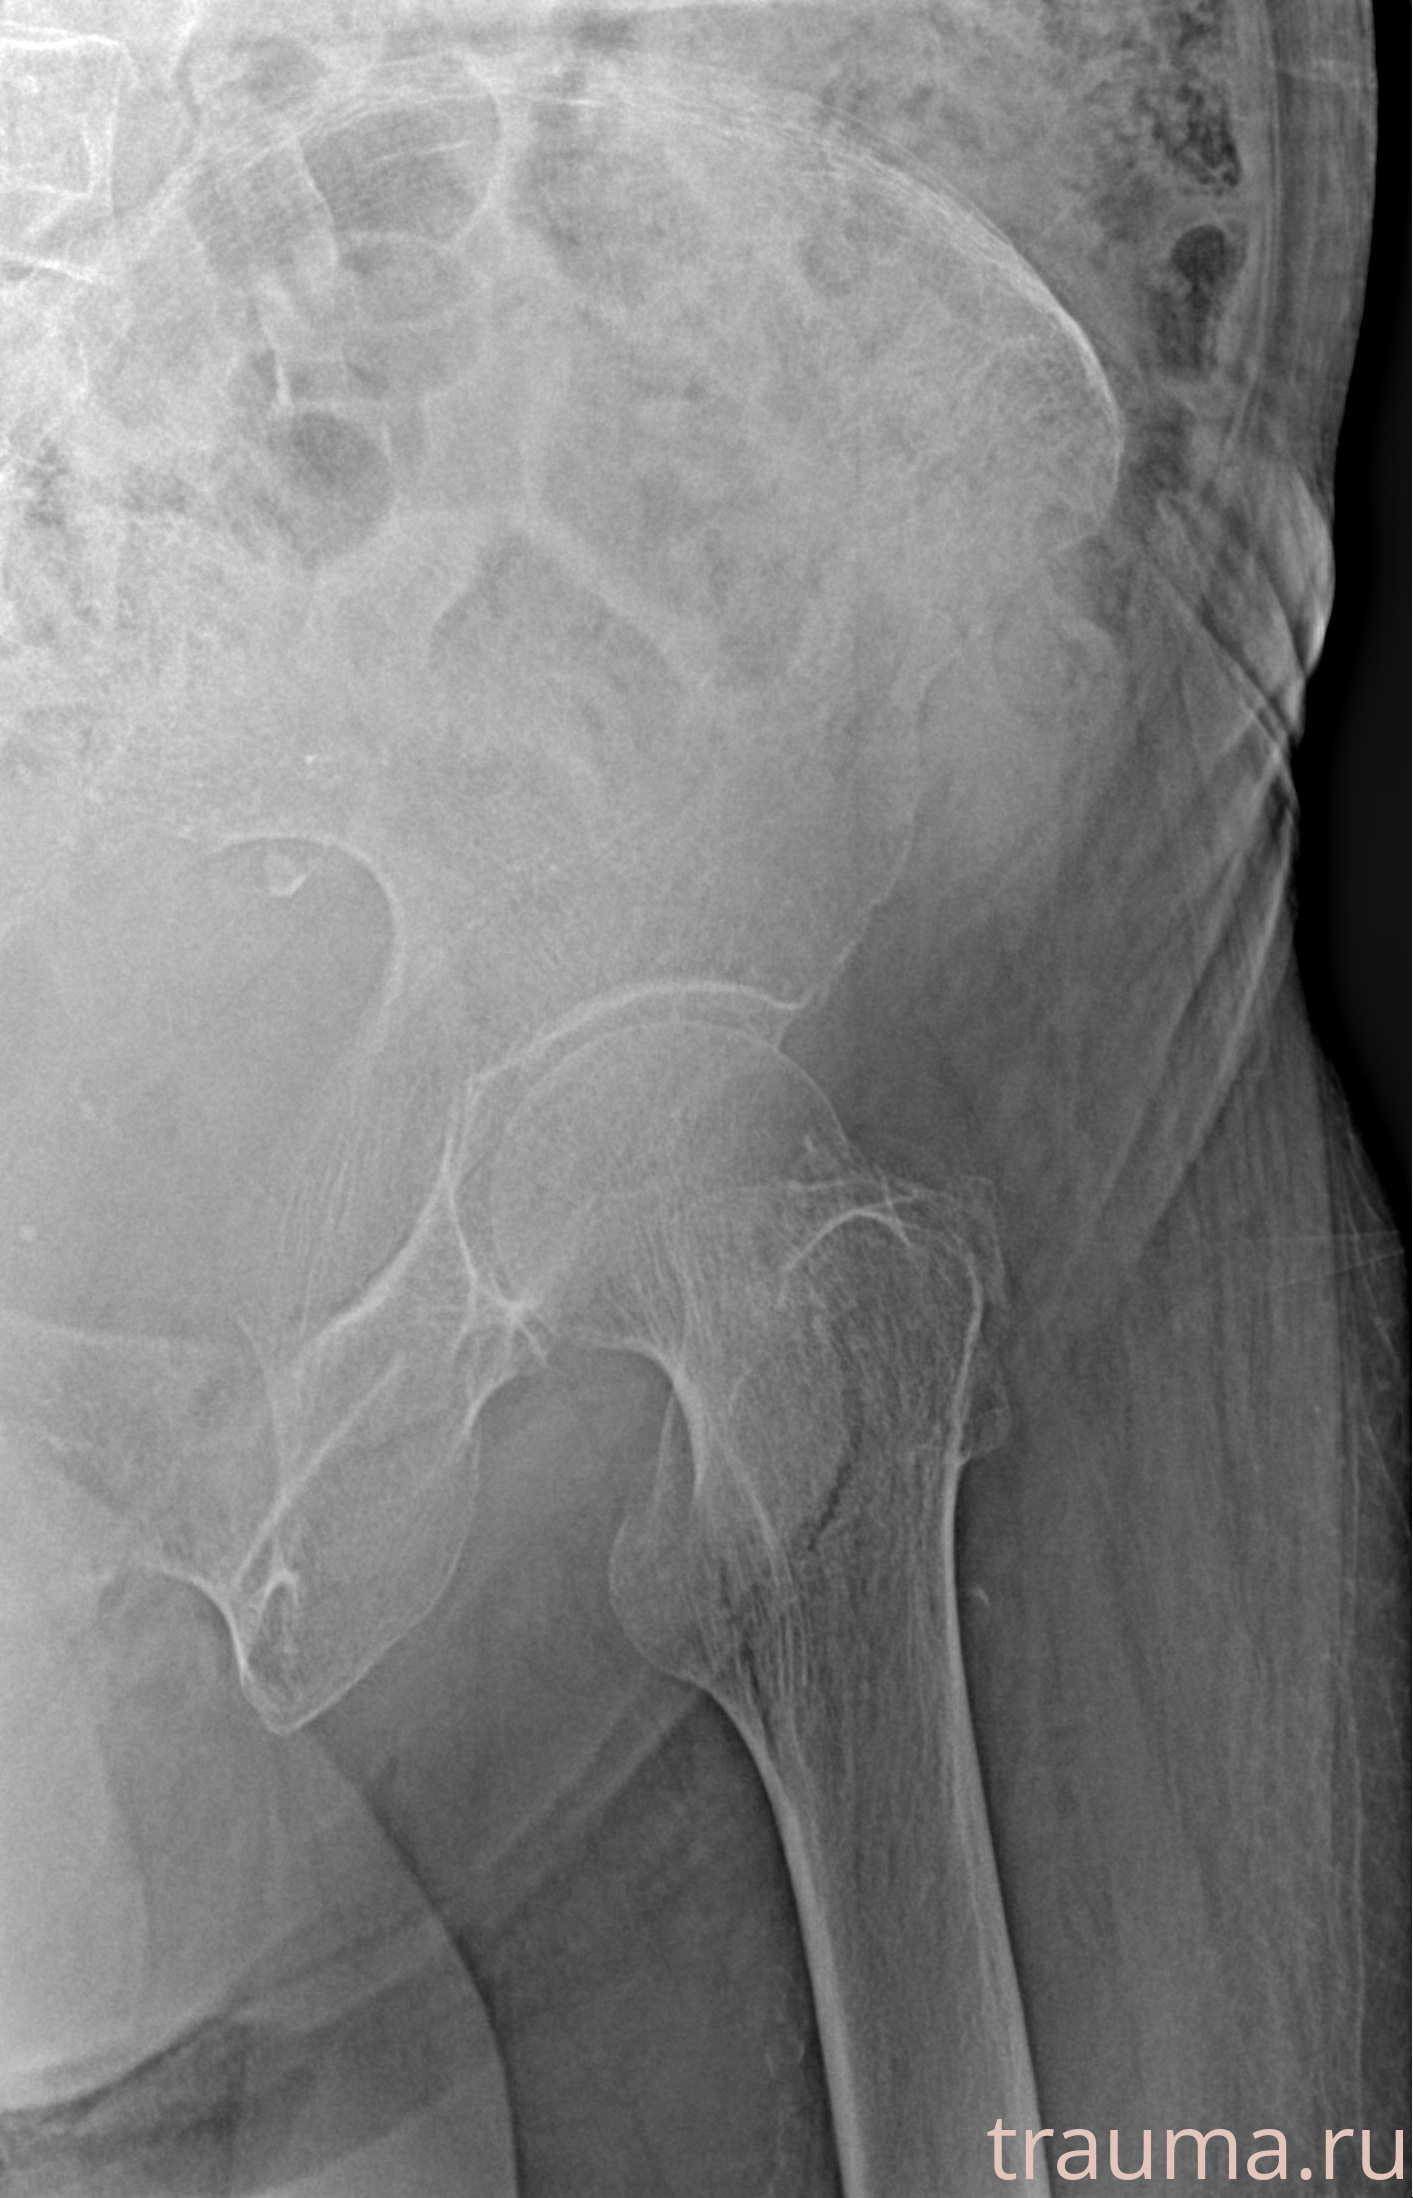

Рентгенограммы

Рентген на дому: по вашему адресу приезжает врач-рентгенолог, травматолог-ортопед с мобильным рентгеновским аппаратом, проводит диагностику травмы или заболевания, делает необходимые рентгенограммы, дает рекомендации по дальнейшему лечению. Получить качественные снимки в домашних условиях возможно благодаря уникальной методике, разработанной МосРентген Центром для института  Склифосовского

при переломе шейки бедра и пневмонии от компании МосРентген Центр - партнера Института имени Склифосовского